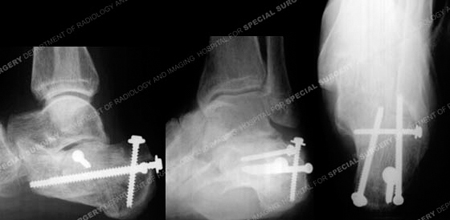

Radiographs 6 months following fracture surgery revealing a healed calcaneus fracture in excellent alignment.

A 68-year-old male was involved in a motor vehicle accident when the car he was driving was struck from behind and pushed into the vehicle in front of him. He was brought to the HSS Orthopedic Trauma Service with complaints of left foot pain and radiographs revealed a left-sided, displaced, intra-articular calcaneus (heel bone) fracture with a depressed articular segment. Fracture surgery was performed by Dr. David L. Helfet using a minimally invasive technique with elevation of the depressed segment, reduction and fixation of the posterior facet and tuberosity including interfragmentary lag screws. He returned at regular follow-up intervals and healed uneventfully, and at 6 months following surgery he presented with good radiographic and clinical results including a healed calcaneus fracture, significant improvement of pain symptoms, and a return to his prior activities of daily living.